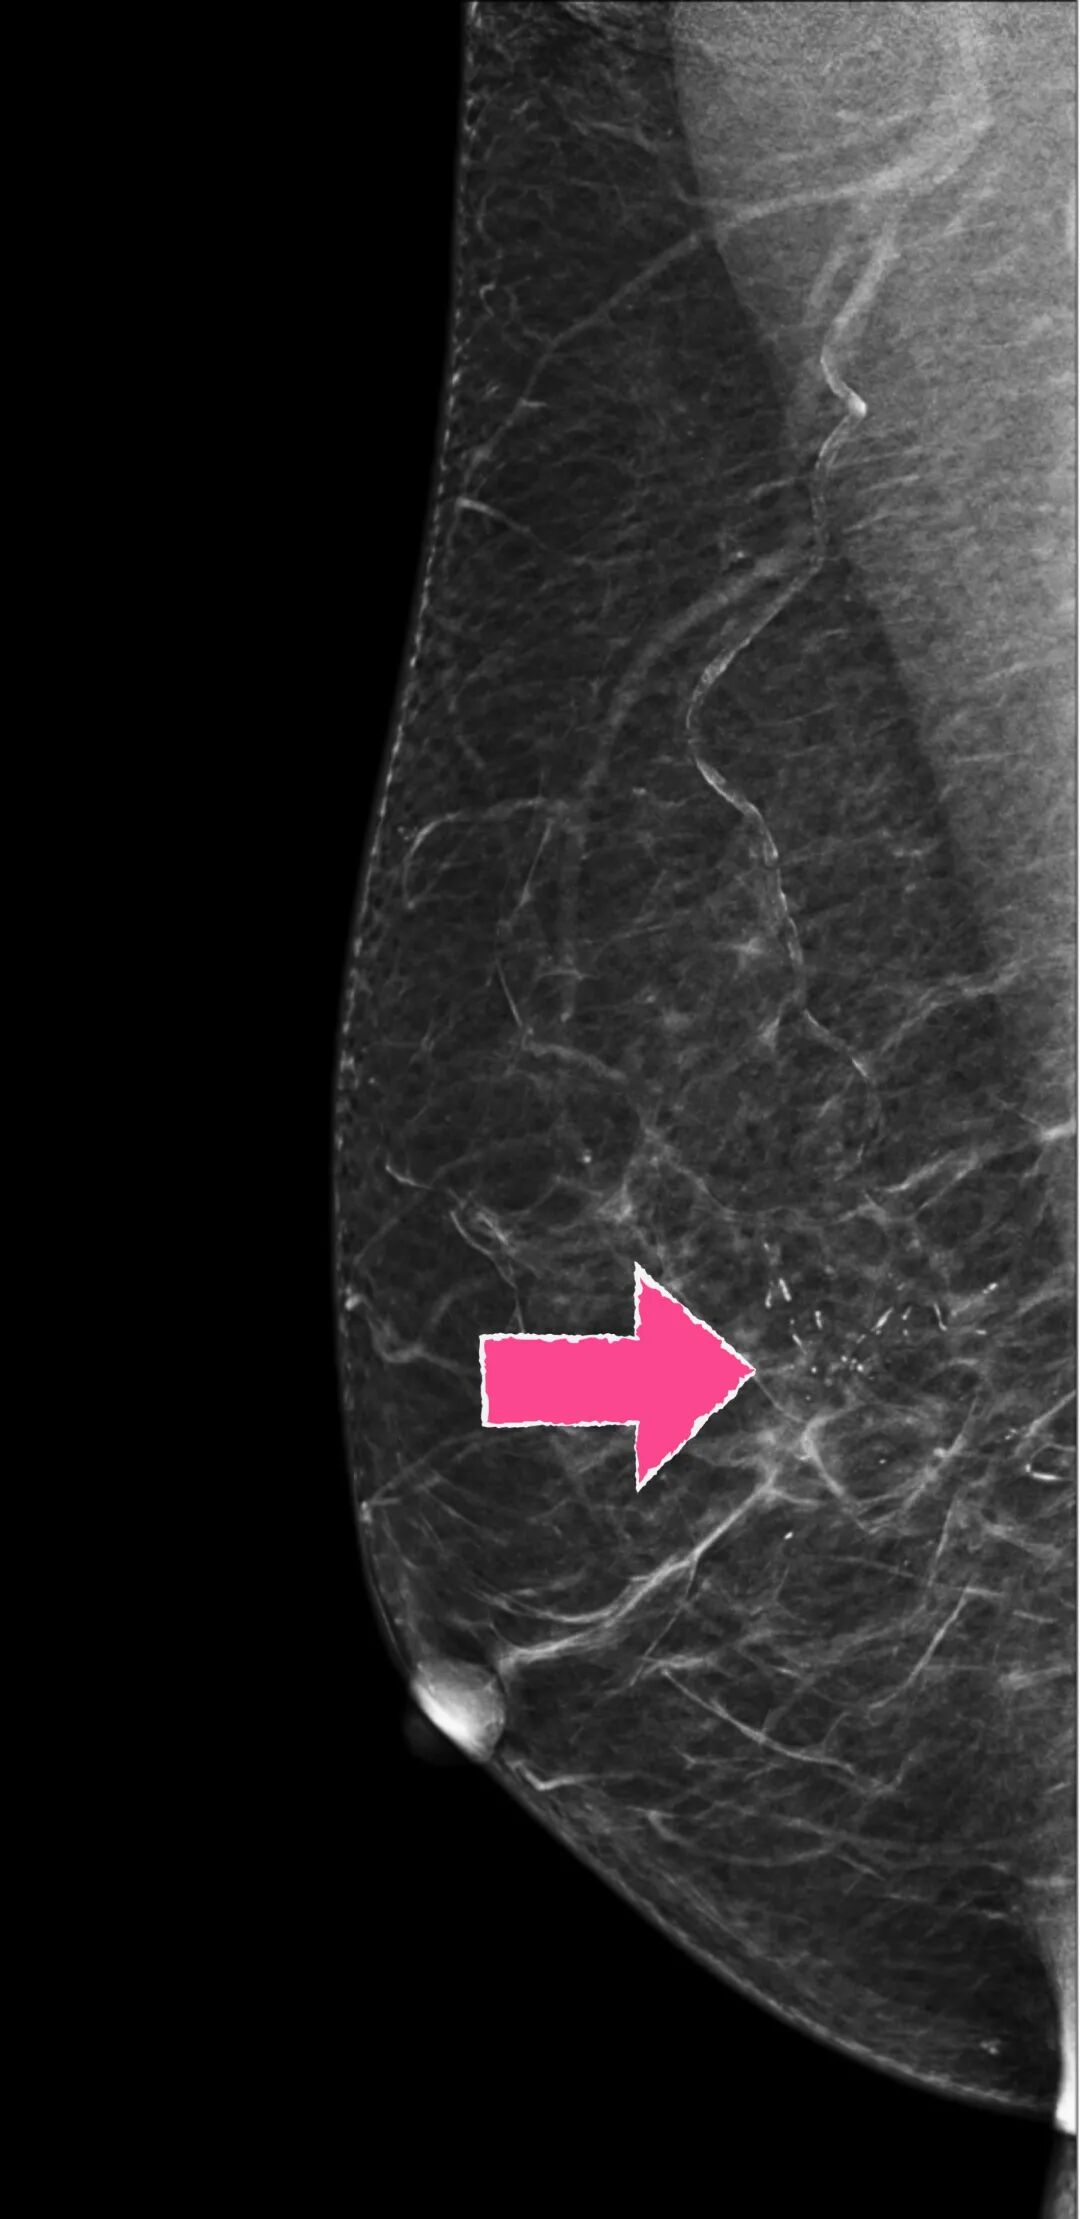

实际上,真正需要警惕的乳腺病变,除了那些“长的叛逆”的肿块,还有一些早期高风险的病灶,有的仅仅表现为乳腺钼靶上不起眼的“成簇小芝麻点状”的或者不定形钙化灶。

这类病灶哪怕个头再小,再不起眼,也得想办法“取”出来“查明身份”。

比如这种👇

▲某患者体检发现右乳钙化灶,放射科提示可疑恶性钙化(“小白点”)

但在大部分手术中,这小钙化灶在B超上是看不到的,开刀时更是看不见摸不着,给乳腺癌早期筛查带来极大障碍。